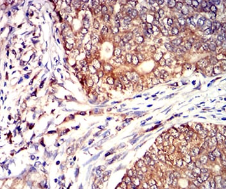

CD53 Mouse Monoclonal antibody[7A8D3]

IHC    1/200 - 1/1000